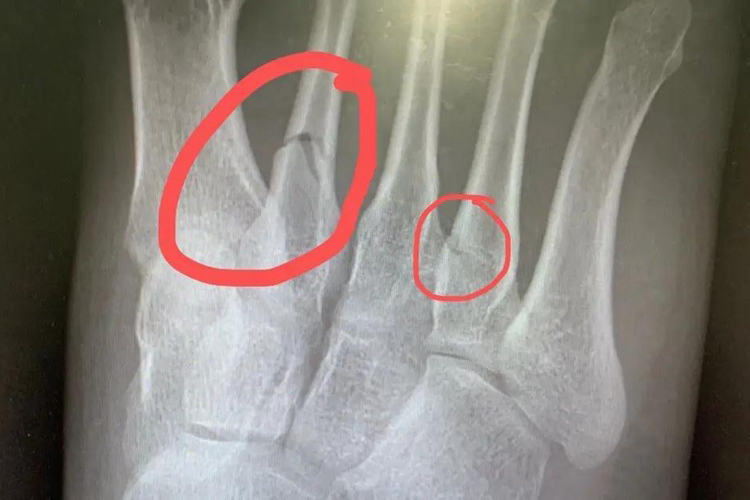

- 骨折愈合的过程涉及多个阶段,从最初的炎症反应、软骨痂形成,到硬骨痂的建立,最后是骨重塑期,在这个过程中,骨折线的消失通常发生在硬骨痂形成之后,此时新生的骨组织填充了骨折间隙,使得X光片上原本可见的断裂痕迹逐渐模糊乃至消失,但是这仅是愈合过程的一部分。

- 骨折初期,血液凝固形成血肿,引发局部炎症,这是愈合的第一步,大约一周后,软骨细胞开始在骨折两端生长,形成软骨痂,为后续硬骨形成打下基础,接下来的几周至几个月内,软骨组织逐渐被钙化的硬骨取代,骨折线开始变得不明显,硬骨痂形成后,进入长达数月至数年的重塑期,骨骼结构和强度逐渐恢复正常,骨折线最终消失。